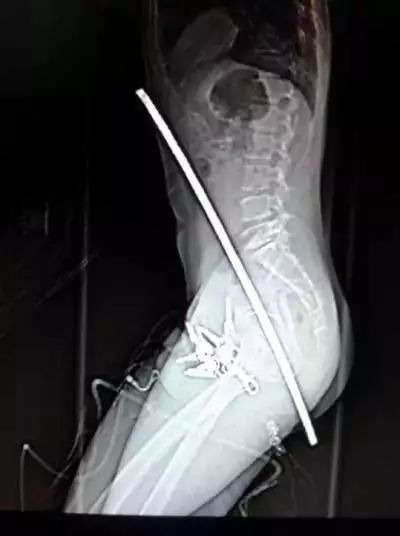

4、安徽合肥,一名建筑工人从2.4米高的脚手架上不幸失足落下,从臀部到胸口被一根钢筋穿透,生命垂危。他的工友们立即将他送到医院救治,他后来被抢救了过来,大难不死。